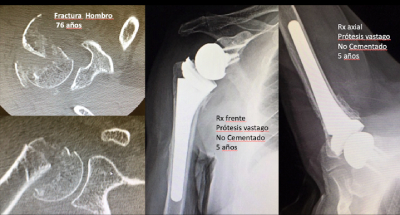

El estudio también analiza características del implante que pueden influir en la recuperación, como la combinación de un vástago rectangular no cementado y sin tornillos, diseñada para permitir una reconstrucción más anatómica y resultados más consistentes en pacientes mayores.

Los datos obtenidos respaldan el papel de la fijación no cementada en este contexto clínico: "Nuestro trabajo demuestra que el vástago no cementado en la prótesis reversa proporciona mayor estabilidad inicial, facilita la consolidación de los tubérculos y se asocia a mejores resultados funcionales y menor tasa de complicaciones. En la práctica, esto implica cirugías más seguras y predecibles, una recuperación más rápida y una mayor fiabilidad de la prótesis reversa en pacientes mayores", concluye.

Además de liderar el estudio, el Dr. Hachem aplica este enfoque quirúrgico desde 2016 en Centro Médico Teknon, integrándolo en su práctica habitual en el tratamiento de pacientes que requieren una prótesis reversa de hombro usando este vástago no cementado con una configuración lateralizada.